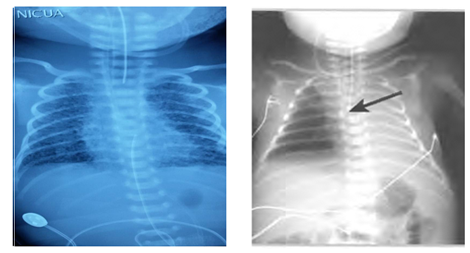

2. Tube in right main bronchus

► Breath sounds only on right chest

► No air heard entering stomach

► No gastric distension

► Action

♦ Withdraw the tube

♦ Recheck air entry

3. Correct placement of tube